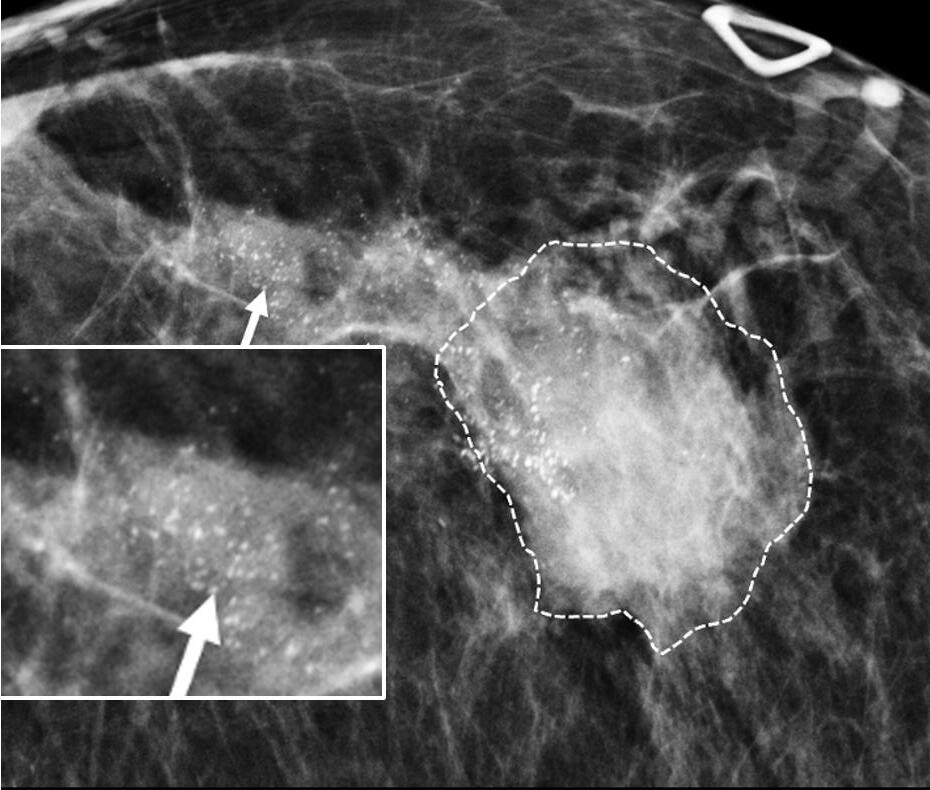

Digital Mammography Breast cancer staging should include bilateral digital diagnostic mammograms (preferably 3D mammograms or tomosynthesis) to evaluate the extent of disease. Although cryoablation is generally performed under ultrasound or CT-scan guidance, high-quality mammography might reveal additional areas of cancer in the same region of the breast (multifocal cancer) or in a different region of the breast (multicentric cancer) that might impact patient selection or alter the cryoablation treatment plan. Multicentric and multifocal breast cancer is generally regarded as a contraindication to cryoablation. Pre-treatment assessment of the mammograms should seek detection of spiculations (radial tumor extensions) and/or microcalcifications that might reach beyond the main tumor mass and require incorporation in the cryoablation treatment zone (Image 1). Since mammography is the only imaging study that reliably shows microcalcifications, mammography plays a particularly important role in determining disease extent when suspicious microcalcifications are part of the disease process. Consequently, patients who are generally opposed to obtaining screening mammograms should be encouraged to have at least one set of pre-treatment diagnostic mammograms to exclude the presence of suspicious microcalcifications that could impact patient selection and/or treatment planning.

Image 1. Mammogram showing density corresponding to a palpable mass (see dashed lines) as well as suspicious microcalcifications (arrows) and inset image showing magnified view of white punctate calcifications extending beyond the palpable mass.